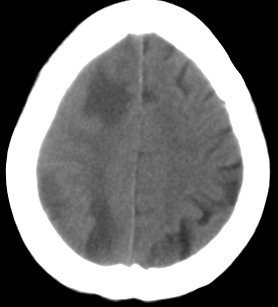

周*,女,78岁,阵发性意识障碍月余,查体四肢肌张力可,病理反射未引出。有脑哽塞病史

右颞顶枕叶多发低密度影,同侧脑室受压变形,病变有明显占位效应.考虑脑肿瘤性病变,建议增强!!!

影像表现: 右侧额、颞、顶叶多发等、低密度区,部分呈结节灶,灶周有不同程度水肿,散在发生,占位效应较重,感觉不是一个整体性病灶,病灶形态呈不规则状明显不同于mca供血区梗死,病变累及基底节区白质。

诊断:右侧额、颞、顶叶肿瘤性病变,首先考虑转移瘤。建议胸片。需与胶质瘤、mca供血区梗死以及脱髓鞘改变区别。

右侧颞,顶叶水肿呈指状,右额叶可见条形低密度带,右侧脑室明显受压,支持右侧脑实质多发转移瘤,建议增强,或拍胸部x片。

右颞顶枕叶多发低密度影,同侧脑室受压变形,病变有明显占位效应,建议增强.

病灶周围脑实质受压明显,右侧脑室受压变形,脑沟明显变浅。支持脑内肿瘤的第一诊断,(不知病人曾经的脑梗塞是否诊断明确),其次考虑脑梗塞的诊断(看起来不大像)

病史:女,78岁,阵发性意识障碍月余,查体四肢肌张力可,病理反射未引出。可基本除外缺血性病变。[br]影像表现: 右侧额、颞、顶叶多发等、低密度区,部分呈结节灶,灶周有不同程度水肿,散在发生,占位效应较重,感觉不是一个整体性病灶,病灶形态呈不规则状明显不同于mca供血区梗死,病变累及基底节区白质。[br]诊断:右侧额、颞、顶叶肿瘤性病变,首先考虑转移瘤。建议胸片。需与胶质瘤、mca供血区梗死以及脱髓鞘改变区别。

右侧额叶大片状水肿,呈指状改变,周围脑沟脑裂消失,右侧脑室受压缩小,提示占位效应明显,平扫未见明显瘤体,单纯从ct片上看可考虑肿瘤,转移瘤或胶质瘤,建议mri检查,以明确诊断.

右侧额、颞、顶叶多发不同程度低密度水肿区,可见占位效应

首先考虑右侧额、颞、顶叶肿瘤性病变,转移瘤可能性大。(部分病灶可能是梗塞性改变)